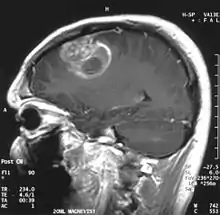

Glioblastome multiforme

Le glioblastome est la tumeur primitive du cerveau la plus fréquente et la plus agressive.

La tumeur peut prendre des apparences variées, en fonction de l'étendue de l'hémorragie ou de la nécrose, ou de son âge. Une scanographie (CT scan) montre généralement une masse non homogène avec un centre hypodense étendu en un anneau de taille variable entouré d'œdème. Il existe un effet de masse avec un déplacement possible du ventricule latéral et du troisième ventricule.